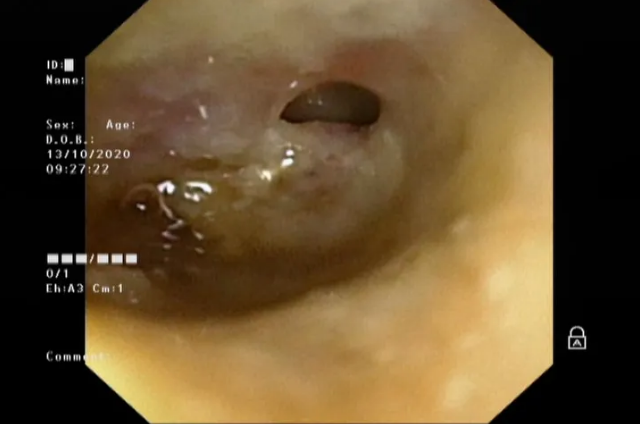

鼓膜上方已穿孔

电子耳内镜下,耳鼻喉科医生看到鼓膜上方有穿孔,还在往外流脓。诊断结论为外伤感染引起的化脓性中耳炎。首先要进行抗感染治疗,再配合洗耳朵、做理疗,来促进感染吸收,避免影响听力。“如果反复化脓感染控制不住,会引起永久性穿孔,将来还得做鼓膜穿孔修补术。”副主任李莉萍说。经过一周治疗,10月20日淘淘出院了。